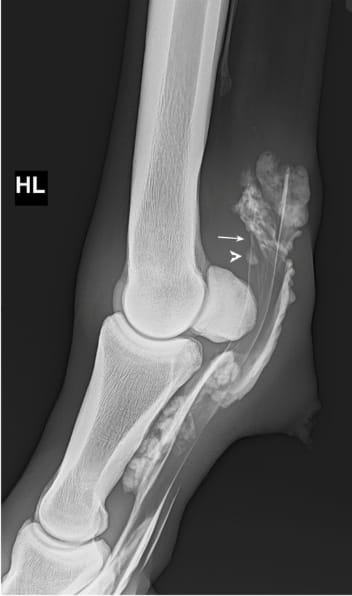

Lateromedial contrast radiograph demonstrating two diagnostic criteria used for assessment of manica flexoria lesions. The two parallel lines which delineate the manica flexoria just above the proximal sesamoid bones, at the dorsal border of the deep digital flexor tendon, are not visible (arrow), and there is an isolated area of contrast overlying the dorsal border of the deep digital flexor tendon at the level of the manica flexoria (arrowhead).